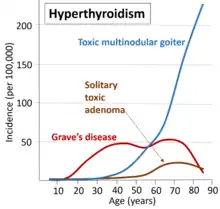

Graves' disease develops in about 0.5% of males and 3.0% of females.[5] It occurs about 7.5 times more often in women than in men.[1] Often, it starts between the ages of 40 and 60, but can begin at any age.[6] It is the most common cause of hyperthyroidism in the United States (about 50 to 80% of cases).[1][4] The condition is named after Irish surgeon Robert Graves, who described it in 1835.[6] A number of prior descriptions also exist.[6]

The goiter in Graves' disease is often not nodular, but thyroid nodules are also common.[19] Differentiating common forms of hyperthyroidism such as Graves' disease, single thyroid adenoma, and toxic multinodular goiter is important to determine proper treatment.[19] The differentiation among these entities has advanced, as imaging and biochemical tests have improved. Measuring TSH-receptor antibodies with the h-TBII assay has been proven efficient and was the most practical approach found in one study.[20]

Graves' disease occurs in about 0.5% of people.[4] Graves' disease data has shown that the lifetime risk for women is around 3% and 0.5% for men.[39] It occurs about 7.5 times more often in women than in men[1] and often starts between the ages of 40 and 60.[6] It is the most common cause of hyperthyroidism in the United States (about 50 to 80% of cases).[1][4]